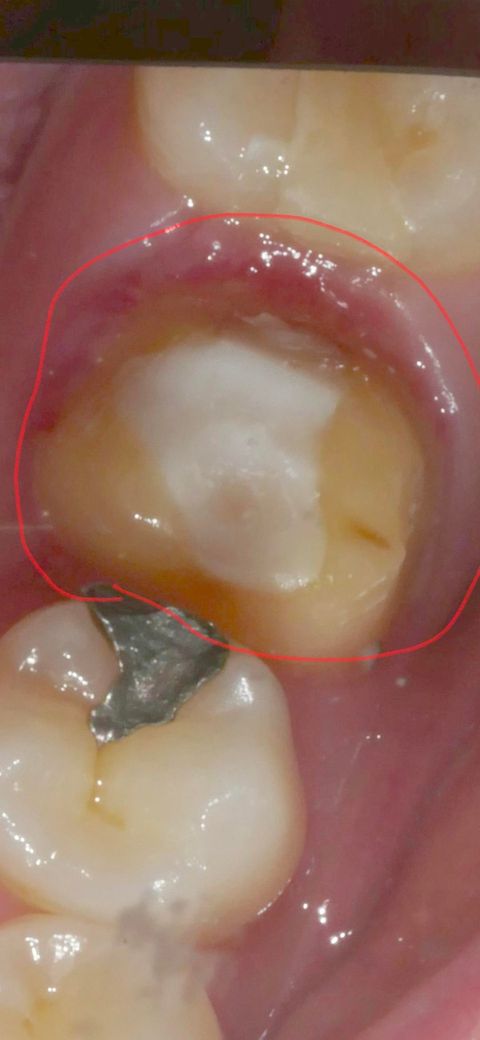

어금니 이대로 크라운 덮어도 괜찮을까요?

신경치료 안한 어금니인데 가운데만 하얗게 뭐가 있는데 레진코어를 하셨다고 하시는데 가운데 하얀부분이 레진코어 인가요? 제가 궁금한 건 이대로 크라운 덮고 나중에 크라운 교체할 때 크라운을 반 갈라서 분리시키는 걸로 알고있는데 저러면 제 생니가 갈릴 수도 있지 않나요? 치아 위로 뭘 더 올려야 하는거 아닌가요? 보통 저렇게 치료 마무리하고 크라운 올려도 될까요?

• 1번 째 사진

네 흰색이 코어레진이 맞습니다

치료에 특별히 문제는 없어보입니다 나중에 문제가 생겨 크라운 뜯는경우 치아가 아주 약간 갈릴 순 있으나 대세에는 지장없습니다 또 치과의사가 알아서 조심스럽게 합니다

레진으로 떼우고 크라운 하는 것이 정상적인 치료법입니다. 크라운 교체할 때 크라운 반으로 분리하는 과정에서 크라운만 삭제하여 제거하는 것은 어려운 것이 아니니 그런 걱정까지 안해도 됩니다.

현재 치료 받은 치아는 마무리가 된 상태로 크라운을 가를 때 본인의 치아는 갈리지 않습니다. 마무리하면 됩니다.

가운데 하얀색이 코어 인거 같고 저상태에서 일반적으로 본을 뜨고 크라운 치료를 마무리 합니다.